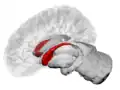

Caudate nucleus (in red) shown within the brain

The caudate nucleus is one of the structures that make up the corpus striatum, which is a component of the basal ganglia in the human brain.[1] While the caudate nucleus has long been associated with motor processes due to its role in Parkinson's disease,[2][3] it plays important roles in various other nonmotor functions as well, including procedural learning,[4] associative learning[5] and inhibitory control of action,[6] among other functions. The caudate is also one of the brain structures which compose the reward system and functions as part of the corticobasal gangliathalamic loop.[1]

The caudate nuclei are located near the center of the brain, sitting astride the thalamus. There is a caudate nucleus within each hemisphere of the brain. Individually, they resemble a C-shape structure with a wider "head" (caput in Latin) at the front, tapering to a "body" (corpus) and a "tail" (cauda). Sometimes a part of the caudate nucleus is referred to as the "knee" (genu).[7] The caudate head receives its blood supply from the lenticulostriate artery while the tail of the caudate receives its blood supply from the anterior choroidal artery.[8]